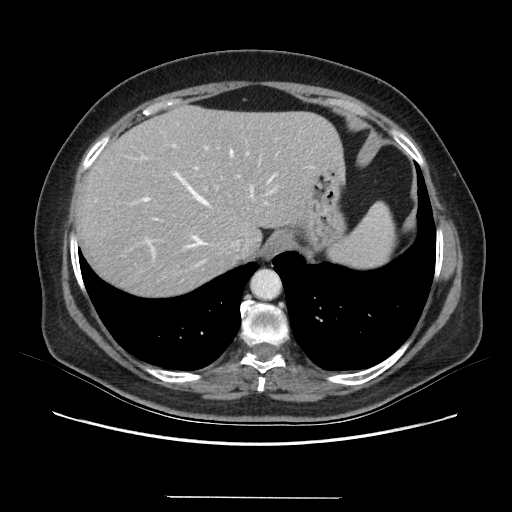

Generated VENOUS CT scan (A→B translation)

Full window (WL 1023.5, WW 4095 β†’ Low βˆ’1024, High +3071)

Lung window (WL -600, WW 1500 β†’ Low βˆ’1350, High +150)

Mediastinum window (WL 40, WW 400 β†’ Low βˆ’160, High +240)